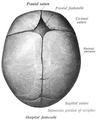

Sagittal suture 2.jpg

Human adult skull from above. Sagittal suture labeled at center.